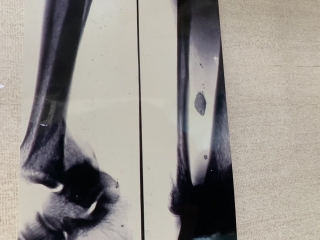

下腿骨下部骨幹部骨折

男子 13歳 サッカーの練習中、タックルされた際受傷する。中下三分の一の骨折です。

受傷時のレントゲン写真。

4週間後